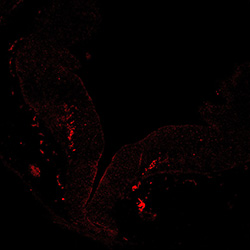

TH

6PCW human midbrain